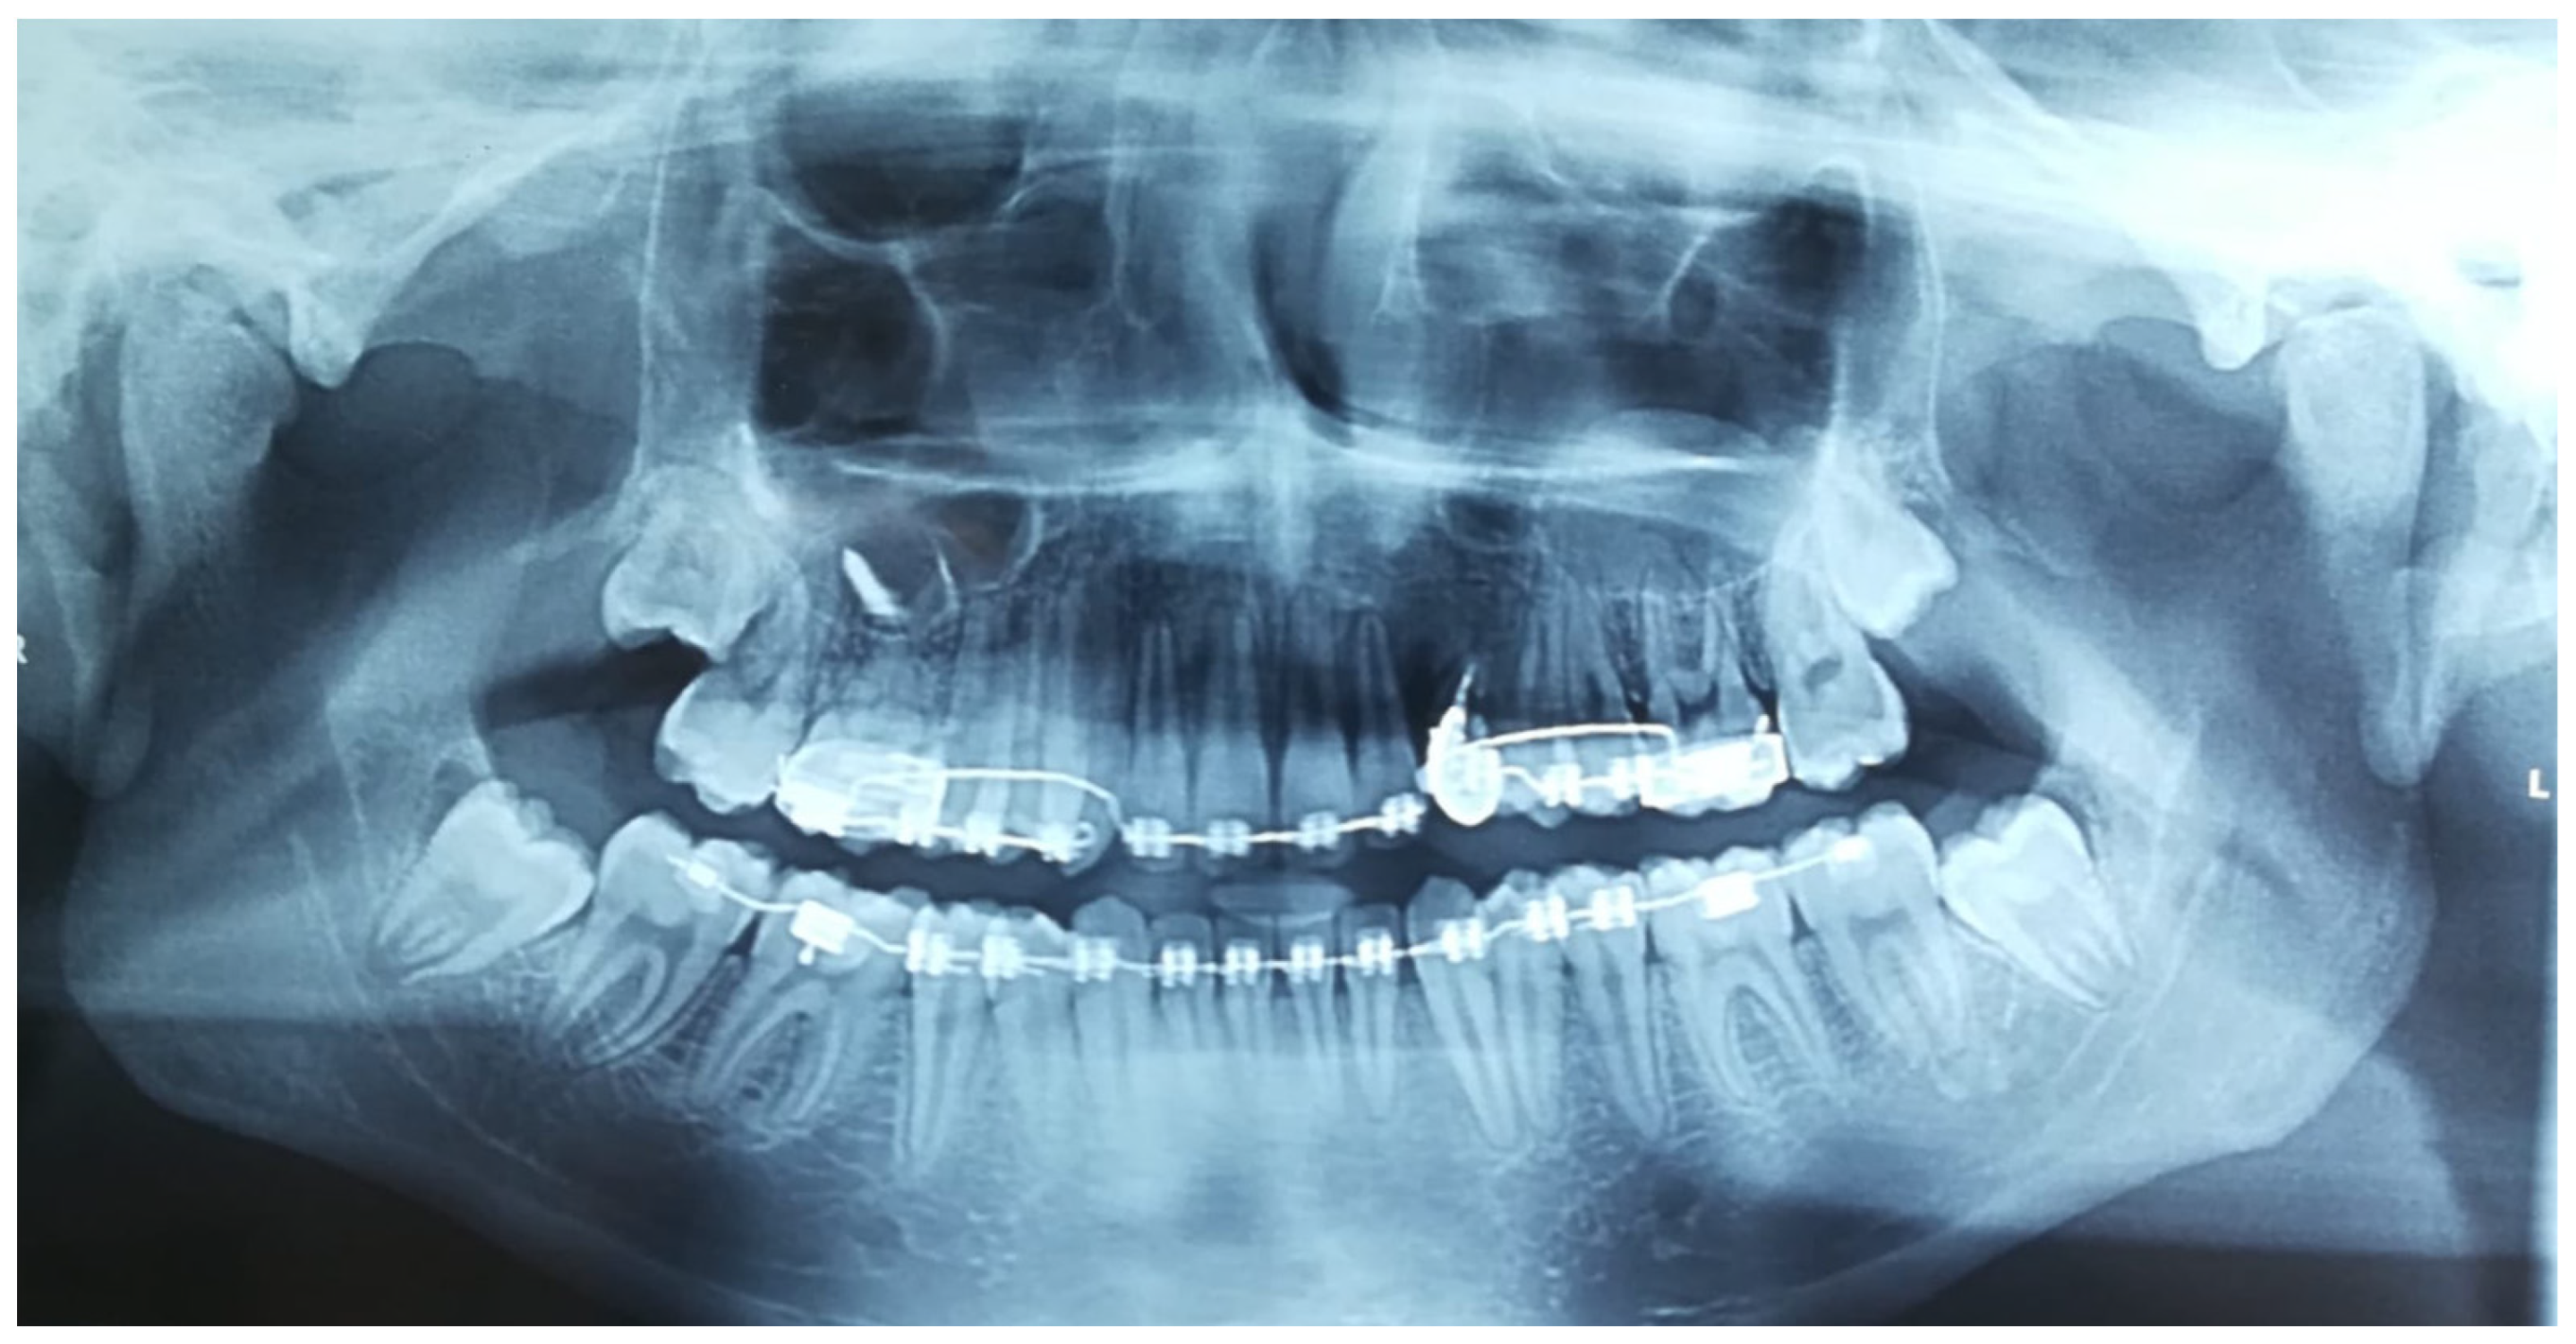

2.2. Radiographic Findings